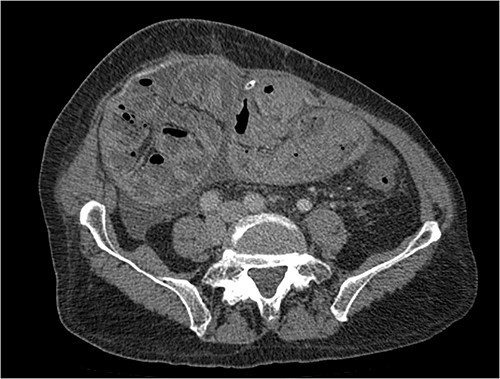

His clinical history and contrast-enhanced computed tomography (CT) findings (Figs 1–3) were compatible with EPS in Stage 4 (Table 2). Laboratory tests were non-specific, showing inflammation and malnutrition. He underwent nutritional support, corticosteroids and surgery. In surgery, fibrocollagenous membrane resection and enterolysis were done. Postoperative period was complicated by pneumonia treated with piperacillin+tazobactam and later bacterial peritonitis treated with ertapenem. The patient was discharged after 29 days with adequate nutrition and asymptomatic.

Portal phase coronal section image on CT showing loops wrapped in a membrane-like structure (arrow).

Imaging exams, mainly CT are important to evaluate causes of bowel obstruction [4]. Dilated or non-dilated small intestine loops may be wrapped in a membrane-like structure, proximal bowel dilatation, thickened peritoneum with diffuse or local calcification, and loculated ascites are some of the findings on CT [1, 12]. Barium X-ray provides a clue to bowel encapsulation, showing clustered loops of the small intestine in the center of the abdomen, known as the cauliflower sign [4]. Ultrasound and magnetic resonance imaging may give a clue but are rarely used [1, 12].